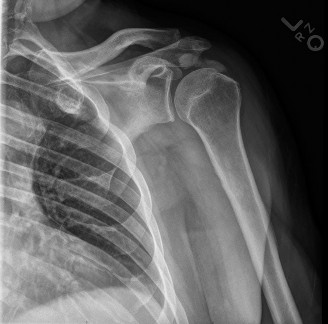

Identify the muscles that compose the force couples in the transverse and coronal planes? CASE 3 A 35-year-old male has had left shoulder pain for 4 months, ever since a low-speed motor vehicle accident (MVA). Physical examination demonstrates preserved range of motion but pain and some weakness with Jobe’s testing. His imaging is shown in Figure 2–8.

Figure 2–8_Reproduced with permission from Stadnick ME. _Partial Rotator Cuff Tears. MRI Web Clinic. 2007 (Apr).

What is the most likely diagnosis?

- Partial articular surface tendon avulsion (PASTA)

- Full-thickness rotator cuff tear

- Superior labrum anterior to posterior tear (SLAP)

- Anterior labral periosteal sleeve avulsion (ALPSA)

Discussion

The correct answer is (A). These are best diagnosed on an MRI as seen in the imaging provided; addition of intra-articular contrast can further improve this study. Answer B, full-thickness rotator cuff tear, is incorrect as the bursal side of the tendon can be seen to be in continuity. Answer C, a SLAP lesion, will be visualized as a labral tear on a coronal MRI and will be found at the biceps root. Answer D, an ALPSA lesion, will be most clearly seen on an axial MRI. It is a variant of a Bankart lesion where the labrum is displaced medially and inferiorly rolling down the glenoid neck underneath the periosteum.